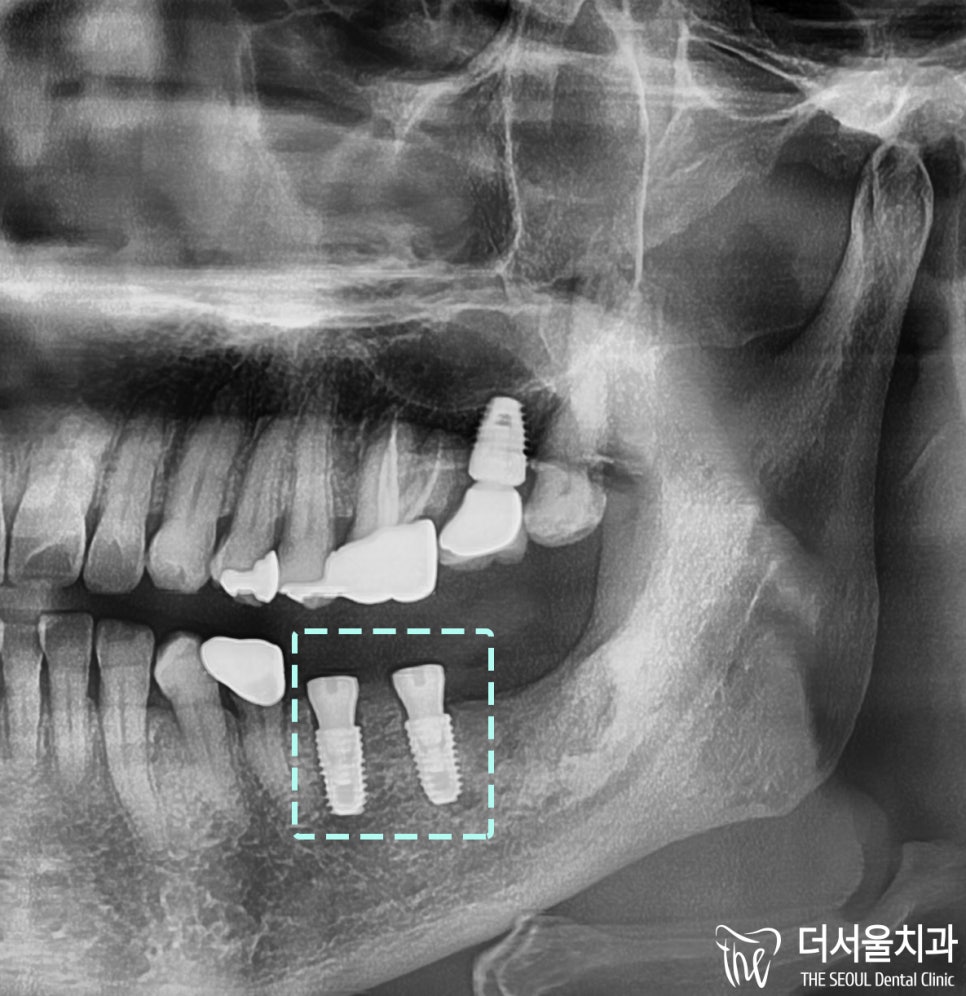

파노라마 사진을 보면

픽스쳐가 나란히 심겨진 것을 볼 수 있는데

워낙, 염증의 범위가 넓었기 때문에

충분한 골융합 기간을 거쳐서

임플란트 크라운을 붙여드리기로 했습니다.

완성된 모습을 보여드리겠습니다.

#27번 임플란트 크라운을

다시 만들어 드렸는다는 점입니다.

즉, 교합이 잘못되어 있어서

어버트먼트(기둥)와 크라운을 다시 제작한 다음

새로운 임플란트 와 교합평면을 맞춰드렸답니다 ~

위로 올라가 있었던 크라운이

아래로 내려온 것을 볼 수 있네요 ^0^